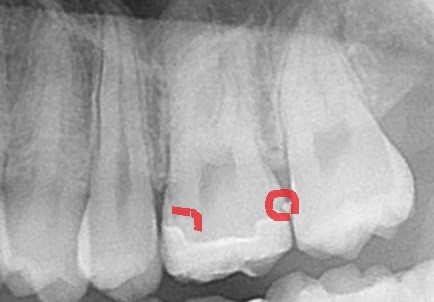

赤い枠の所ですが、右側に白い粒のような出っ張りが。左側には黒い影が見えてきます。

ここから分かることは

- セラミックが上手くセットされていない

- セラミックの中に虫歯が残っている

という事が推測されます。